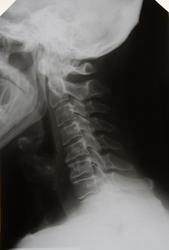

En la actualidad la osteoporosis se diagnostica midiendo la densidad mineral ósea (DMO) y se trata con bifosfonatos. A pesar de que aumentan la DMO, los tratamientos prolongados con este grupo de fármacos pueden provocar un deterioro de la integridad estructural ósea. La calidad ósea viene dada por varios factores, tales como la geometría y la arquitectura óseas o la acumulación de microfracturas. El desarrollo de nuevos métodos de evaluación de la calidad ósea permitiría mejorar el diagnóstico y realizar un seguimiento de su eficacia. El proyecto Bonequal («Evaluación de la calidad ósea en las enfermedades óseas metabólicas») se puso en marcha con el objetivo de cuantificar los efectos del envejecimiento y la osteoporosis en la estructura, la composición y las propiedades mecánicas del hueso esponjoso o trabecular. Para ello, el equipo de investigación de Bonequal realizó biopsias de huesos de cadáveres de personas que habían sufrido enfermedades óseas metabólicas. En el marco del proyecto se desarrolló un nuevo método para calcular la forma tridimensional del fémur mediante una exploración bidimensional de la DMO y una plantilla de una tomografía axial computerizada (TAC). Una vez perfeccionada, esta técnica permitirá realizar estimaciones más precisas del riesgo de fractura en personas con osteoporosis. Gracias a los nuevos métodos desarrollados en el marco de Bonequal para determinar el grado de viscoelasticidad del hueso, se concluyó que esta propiedad disminuye con la edad, dando lugar a una mayor fragilidad en personas mayores. Asimismo, el equipo indagó en la posibilidad de emplear la espectroscopia infrarroja para detectar cambios en la composición ósea de los pacientes, técnica ésta que se reveló muy prometedora como herramienta diagnóstica. Bonequal abrió una nueva vía de investigación en materia de herramientas cuantitativas de radiodiagnóstico al establecer que se precisa una imagen con una resolución en vóxeles inferior a las 100 micras para poder disgregar los parámetros estructurales del hueso esponjoso y realizar un análisis contrastivo del hueso sano y el afectado de osteoporosis. Esta iniciativa ha contribuido al diagnóstico por imagen con nuevos métodos de detección precoz de la osteoporosis que, por otra parte, permiten predecir con más exactitud el riesgo de fractura.